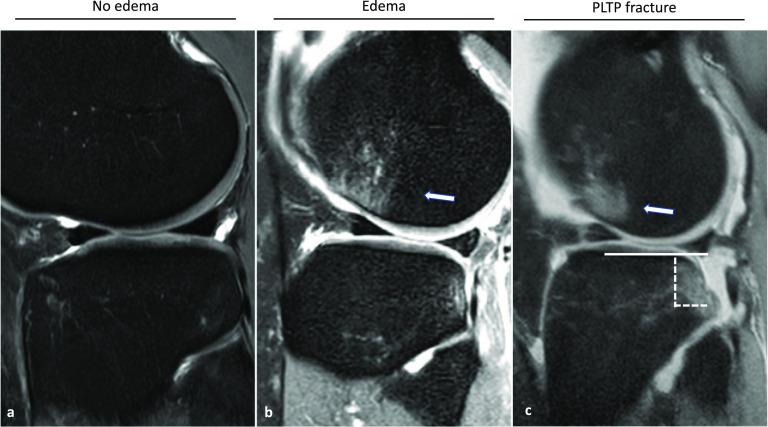

RESULTS

Between January 2017 and December 2018, 151 patients with acute ACL ruptures with a mean age of 32 ± 12 years were included in this study. The MRIs performed during the acute phase were analyzed by four independent investigators-two radiologists and two orthopedic surgeons. The trauma impact on the posterolateral tibial plateau and associated injuries to the medial complex (POL, dMCL, and sMCL) were examined and revealed an injury to the medial collateral ligament complex in 34.4% of the patients. The dMCL was the most frequently injured structure (92.2%). A dMCL injury was significantly associated with an increase in trauma severity at the posterolateral tibial plateau (p < 0.02) and additional injuries to the sMCL (OR 4.702, 95% CL 1.3-133.3, p = 0.03) and POL (OR 20.818, 95% CL 5.9-84.4, p < 0.0001). Isolated injuries to the sMCL were not observed. Significant risk factors for acquiring an sMCL injury were age (p < 0.01) and injury to the lateral meniscus (p < 0.01).

结果

2017年1月至2018年12月期间,本研究纳入了151例急性ACL断裂患者,平均年龄为32±12岁。急性期进行的MRI由四位独立研究者——两位放射科医生和两位骨科医生进行分析。检查了创伤对胫骨后外侧平台的影响以及内侧复合体(后外侧关节囊韧带、深层内侧副韧带和浅层内侧副韧带)的相关损伤,结果显示34.4%的患者存在内侧副韧带复合体损伤。深层内侧副韧带是最常受伤的结构(92.2%)。深层内侧副韧带损伤与胫骨后外侧平台创伤严重程度增加(p<0.02)以及浅层内侧副韧带(比值比4.702,95%可信区间1.3 - 133.3,p = 0.03)和后外侧关节囊韧带(比值比20.818,95%可信区间5.9 - 84.4,p<0.0001)的额外损伤显著相关。未观察到浅层内侧副韧带的孤立损伤。获得浅层内侧副韧带损伤的显著危险因素是年龄(p<0.01)和外侧半月板损伤(p<0.01)。